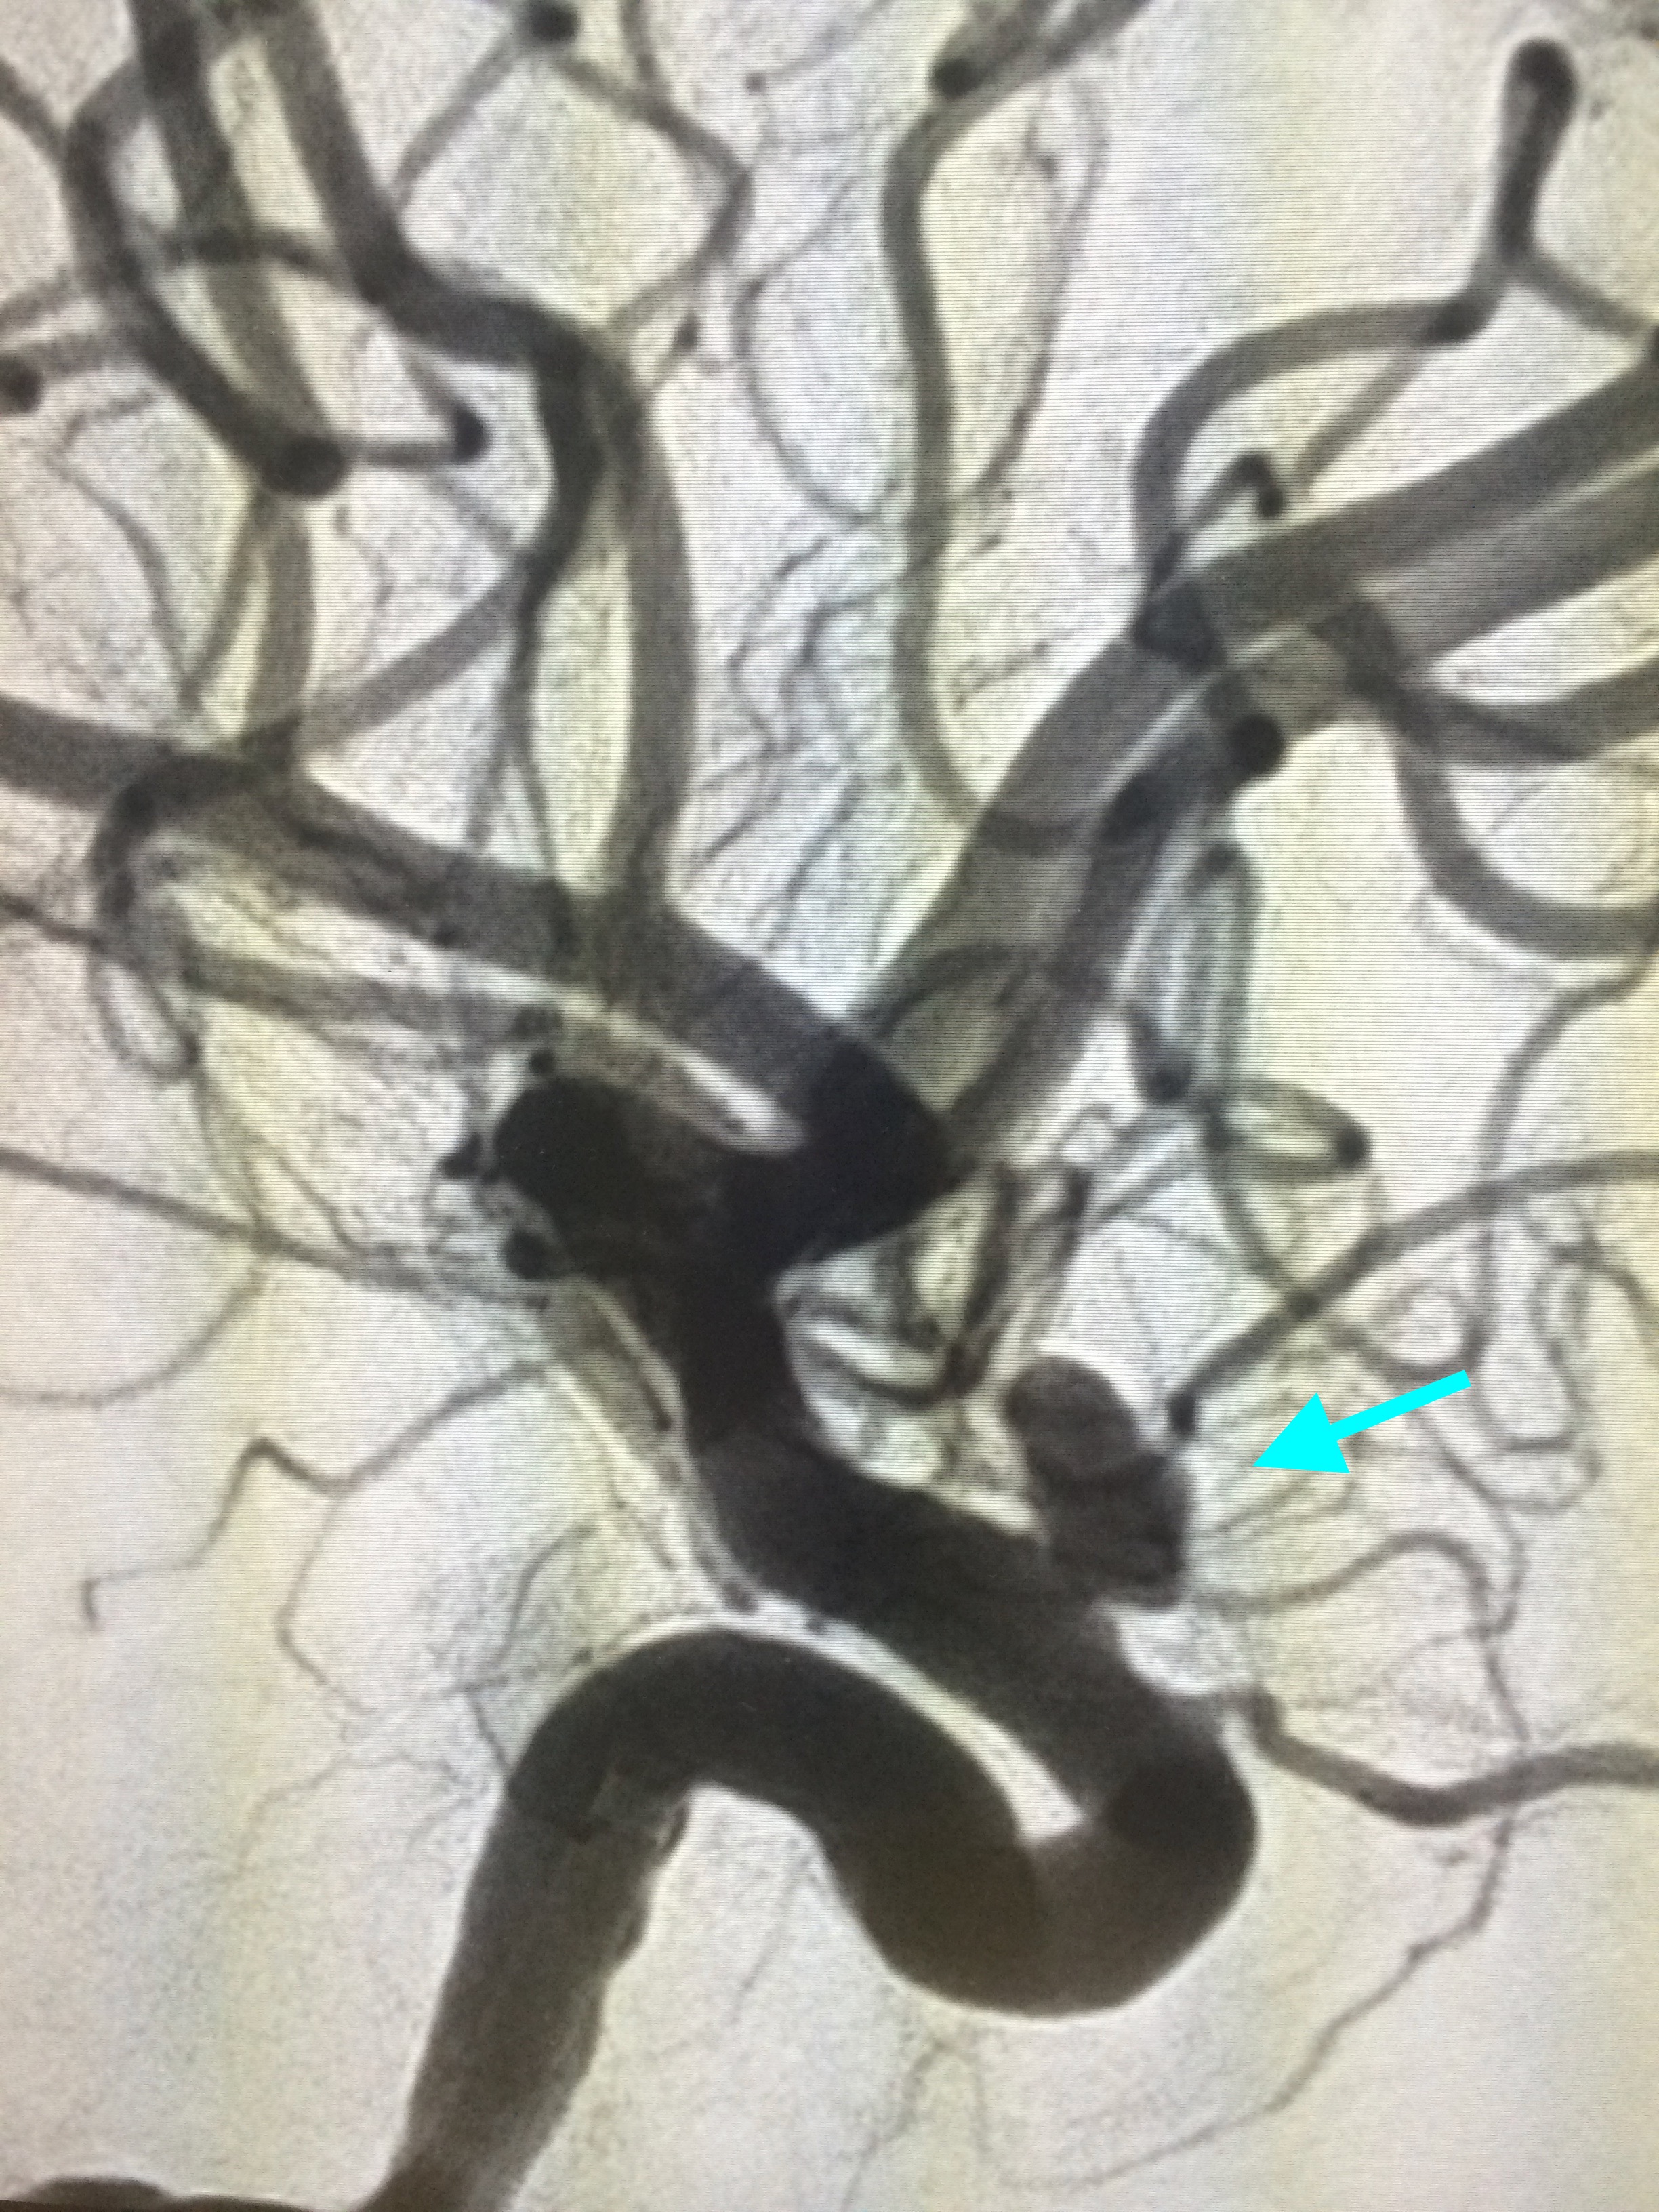

The Myth That Small Brain Aneurysms Don’t Rupture